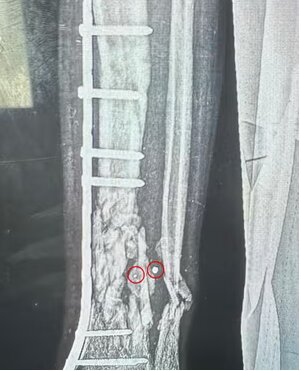

مارک پرلموتر، جراح ارتوپد از کارولینای شمالی، که در بیمارستان سیدوا کار می کرد گفت: کودکان در برابر هر گونه آسیب نافذ آسیب پذیرتر هستند، زیرا جثه کوچکتری دارند. قسمت های حیاتی آنها کوچکتر است و راحت تر از بین می رود. وقتی کودکان دچار پارگی رگ های خونی می شوند، رگ های خونی آن ها آنقدر کوچک است که به سختی می توان آن ها را کنار هم قرار داد. شریان تغذیه کننده ساق، شریان فمورال، تنها به ضخامت یک رشته فرنگی در یک کودک است. خیلی خیلی کوچک است بنابراین ترمیم آن و چسباندن اندام بچه به آنها بسیار دشوار است.». تا حد زیادی شایع ترین زخم ها زخم های ورودی و خروجی یک یا دو میلی متری هستند. اشعه ایکس استخوان های تخریب شده را نشان داد که در یک طرف آن یک سوراخ سوزنی، است و در طرف دیگر استخوانی است که به نظر می رسد یک تایر تراکتور از روی آن عبور کرده است. بچه هایی که ما آنها را عمل کردیم، اکثرشان از این مبادی ورودی و خروجی کوچک داشتند.

پرلموتر توضیح داد که مکرراً با زخم های مشابه مواجه شده است. وی گفت: اکثر بیماران ما زیر ۱۶ سال بودند. زخم خروجی فقط چند میلی متر است. اما می توانید ببینید که به دلیل آسیب هایی که در داخل وارد می کند سرعت بسیار بالایی دارد. هنگامی که چندین تکه کوچک وارد بدن می شود که با سرعت دیوانه وار حرکت می کنند، به بافت نرم آسیب می زند که بسیار بیشتر از اندازه قطعات بزرگ است.